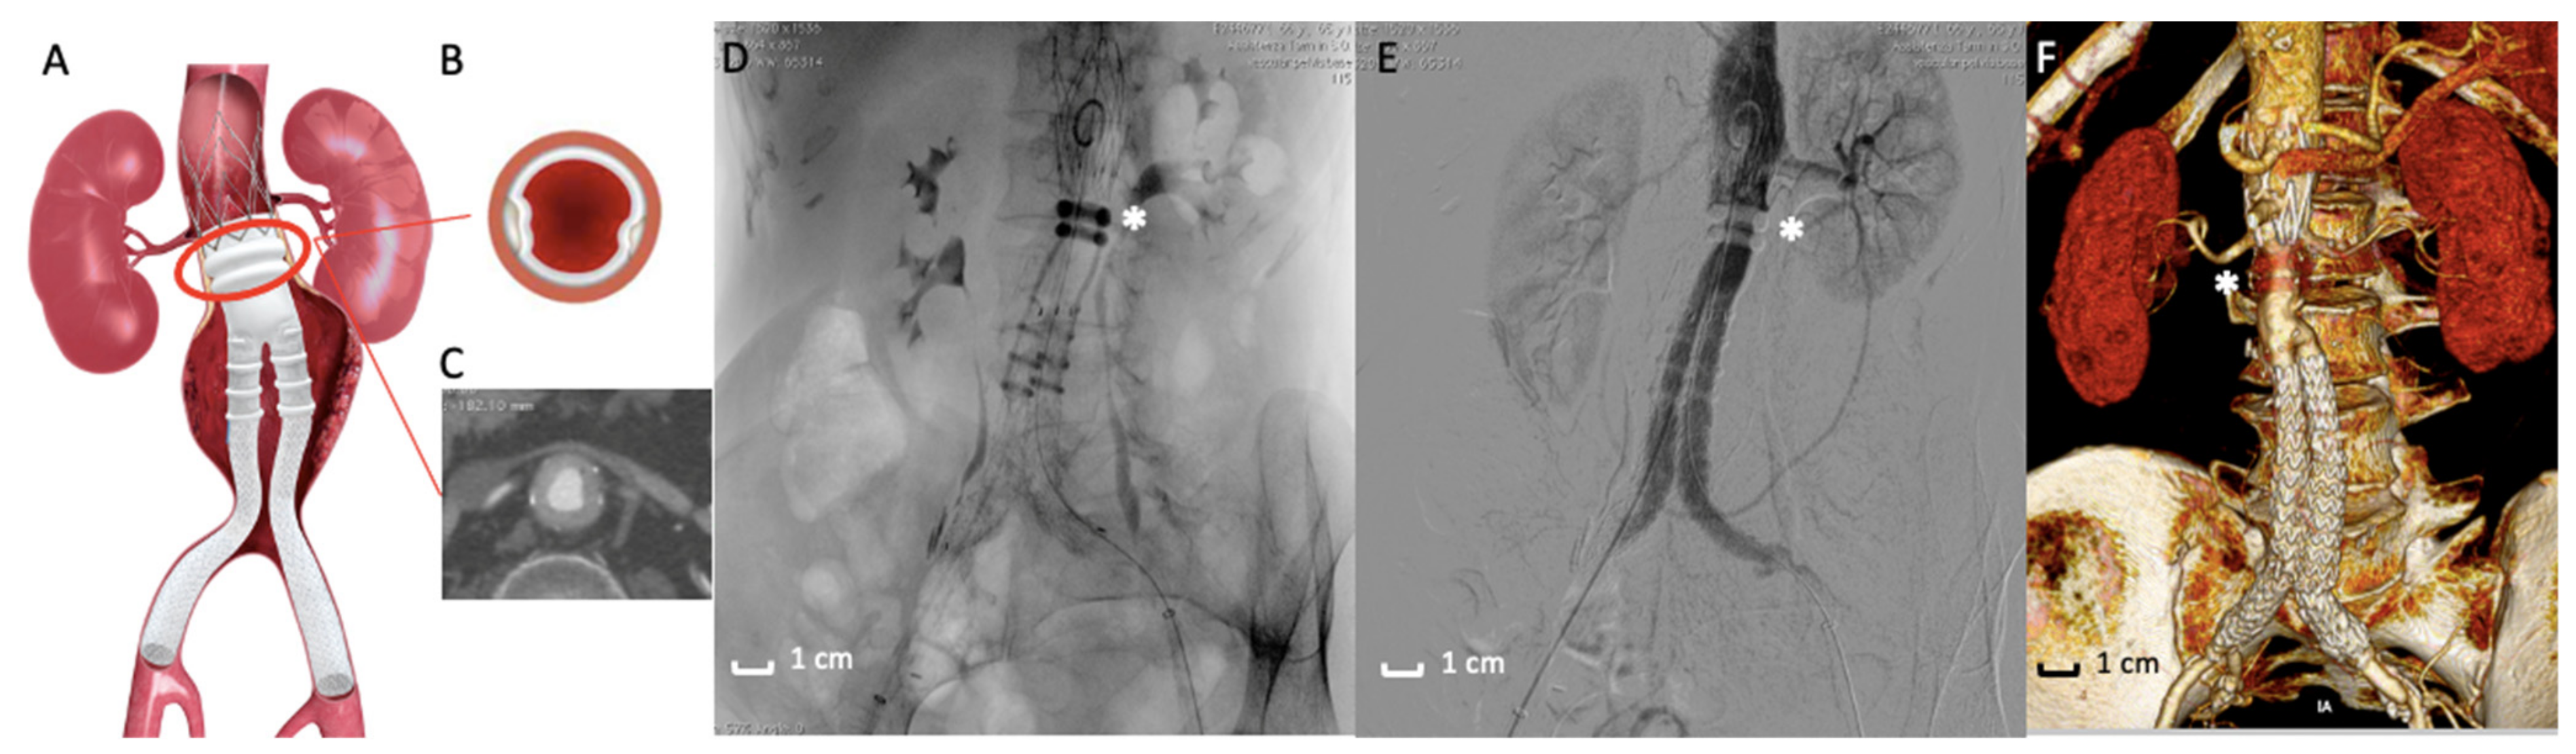

EVAR has gained wide acceptance as the preferred method to treat patients with AAA [1,23,24,25,26,27,28]. The standard endovascular procedure involves a stent-graft that is designed to exclude the aneurysm from the systemic circulation (Figure 1). The stent is made of a metallic skeleton and covered with polytetrafluoroethylene (PTFE) or polyester fabric that keeps the stent impermeable. The device is advanced through the femoral artery using fluoroscopic guidance toward the aneurysm site and then deployed. Sealing the proximal and distal ends of the aneurysm isolates the aneurysm, preventing subsequent rupture. Traditional EVAR devices employ self-expanding stent structures to promote graft-to-aortic wall apposition (seal) and fixation [29,30,31]. The amount of proximal device oversizing with self-expanding stent grafts (SESGs) is known to influences neck progression over time [32]. As a matter of fact, once deployed, SESGs continue to expand until the nominal diameter is reached unless tissue resistance limits expansion. When aortic neck dilation occurs, midterm outcomes are reportedly adverse [33,34].

Figure 1. Traditional stent-graft design. (A) Picture of the endograft deployed in Abdominal Aortic Aneurysm. Traditional Endovascular aneurysm repair (EVAR) devices employ self-expanding stent structures to promote graft-to-aortic wall apposition (seal) and fixation. (B) Intraoperative fluoroscopic image of the endograft deployed in the abdominal aortic aneurysm (AAA). (C) Angiographic acquisition that reveals a good exclusion of the AAA and the good patency of the endograft. (D) 3D volume rendering of Computed Tomography Angiography at 1-month follow-up that shows the correct aneurysm exclusion.